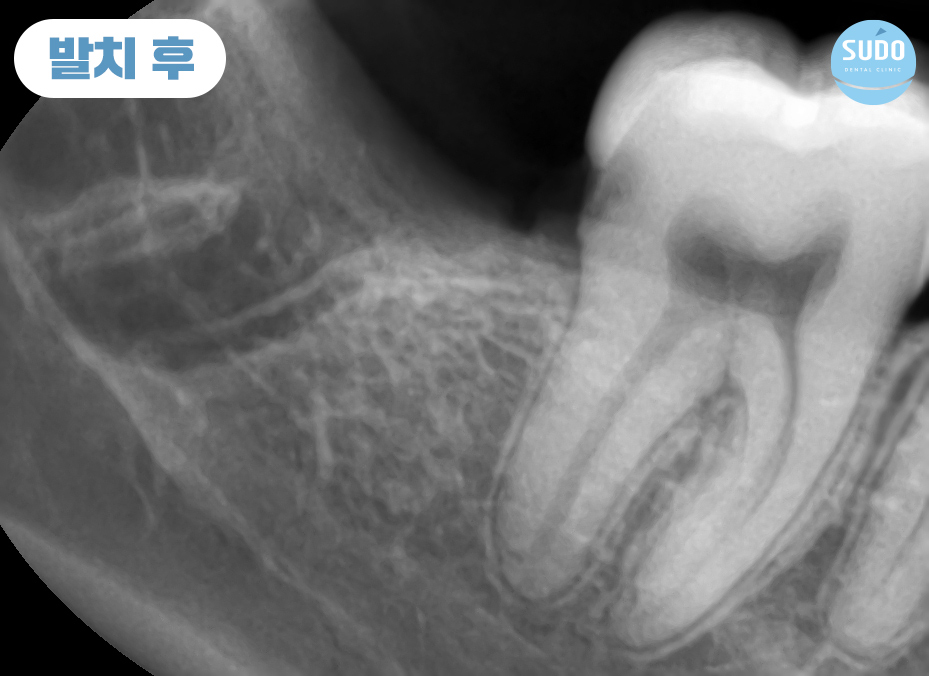

본 환자분은 20대 초반의 남성분으로 오른쪽 아래 매복되어 있는 사랑니에 충치가 심하게 진행되어 치아 일부가 이미 파절된 상태로 본원에 내원해 주셨습니다.

X-ray를 촬영해 보니 치아 뿌리 끝이 신경관과 매우 근접한 상태였습니다. 신경관 손상 가능성이 있어 까다로운 케이스였는데, CT로 촬영하여 정밀 분석한 결과를 토대로 환자분의 충분한 상담을 통해 발치를 진행하기로 했습니다.

특히, 본 환자분과 같이 신경관과 가까이 위치했다면 난도가 높은 과정이 필요한 만큼 의료진의 선택이 더욱 중요해집니다.

파노라마 사진에서 보이는 것과 같이 아래쪽 어금니 아래는 많은 신경들이 지나갑니다.